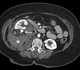

Retroperitoneal hemorrhage

Retroperitoneal bleeding is an accumulation of blood in the retroperitoneal space. Signs and symptoms may include abdominal or upper leg pain, hematuria, and shock. [Source: Wikipedia ]